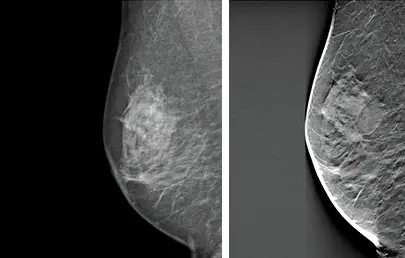

digital vs 3D missed cancer

Cancer visible on the right 3D mammogram but not the left 2D mammogram.

• With a mammogram, glandular and fibrous tissue is white and fat is seen as black

• Cancers are also seen as white so they can hide in normal glandular breast tissue, particularly if the breasts are dense which is seen in our clinic population

• The 3D tomosynthesis takes images through the breast while the mammogram is taken, and the computer reconstructs this into 1mm slices through the breast

• Our specialist radiologist reads this in conjunction with the state of the art 2D digital images

• This improves cancer detection and reduces the number of unnecessary biopsies